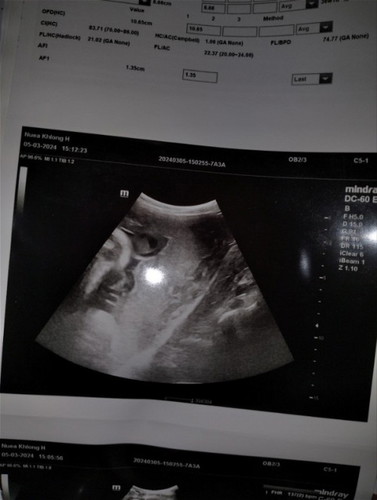

นี้ใช่หน้าน้องหรือเปล่าหรือดูผิดท้องแรกค่ะ 💕🥰 35+3 week